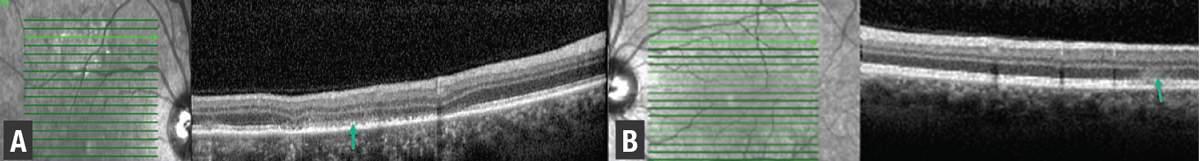

OCT through the superior right macula highlighted retinal pigment epithelial atrophy, ellipsoid zone loss and outer nuclear layer thinning (Figure 3). OCT of the left macula through an active lesion demonstrated hyper-reflectivity of the ONL with underlying EZ attenuation (Figure 3, green arrow).

| Figure 3. Spectral-domain optical coherence tomography of the right eye (A) shows areas of ellipsoid zone and retinal pigment epithelium (green arrow) disruption, while left eye scans (B) superior to the fovea demonstrate hyperreflectivity in the outer nuclear layer with underlying EZ attenuation (green arrow). |